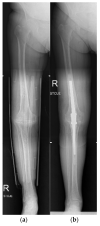

Osteoarthritis is a degenerative condition affecting the whole joint with the underlying bone, representing a major source of pain, disability, and socioeconomic cost worldwide. Age is considered the strongest risk factor, albeit abnormal biomechanics, morphology, congenital abnormality, deformity, malalignment, limb-length discrepancy, lifestyle, and injury may further increase the risk of the development and progression of osteoarthritis as well. Pain and loss of function are the main clinical features that lead to treatment. Although early manifestations of osteoarthritis are amenable to lifestyle modification, adequate pain management, and physical therapy, disease advancement frequently requires surgical treatment. The symptomatic progression of osteoarthritis with radiographical confirmation can be addressed either with arthroscopic interventions, (joint) preservation techniques, or bone fusion procedures, whereas (joint) replacement is preferentially reserved for severe and end-stage disease. The surgical treatment aims at alleviating pain and disability while restoring native biomechanics. Miscellaneous surgical techniques for addressing osteoarthritis exist. Advanced computer-integrated surgical concepts allow for patient personalization and optimization of surgical treatment. The scope of this article is to present an overview of the fundamentals of conventional surgical treatment options for osteoarthritis of the human skeleton, with emphasis on arthroscopy, preservation, arthrodesis, and replacement. Contemporary computer-assisted orthopaedic surgery concepts are further elucidated.